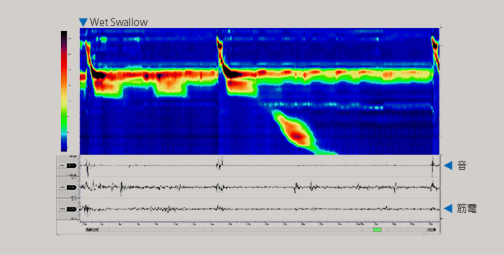

圧力36ch、pH2ch、Z18ch、外部アナログ信号入力16ch、音声1ch、X-ray等のアナログビデオ信号と多種多様な信号をパソコンの1フレームに同時収録します。